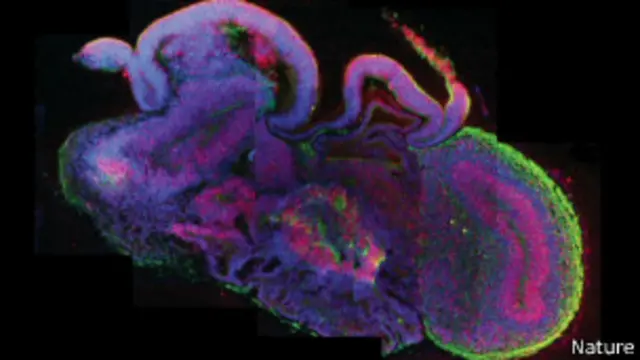

El cerebro humano es una de las estructuras más complejas del Universo. Y aún así, científicos lograron crear en laboratorio uno en miniatura. La hazaña podría transformar el conocimiento que se tiene de enfermedades neurológicas.

La estructura, del tamaño de un guisante, alcanzó el mismo nivel de desarrollo de un feto de nueve semanas de gestación, pero es incapaz de desarrollar pensamiento.

Las células pudieron crecer y organizarse en regiones separadas del cerebro, como el córtex cerebral, la retina y, algo muy raro, un hipocampo prematuro, el cual se cree que está muy involucrado en la memoria del cerebro de un adulto completamente desarrollado.

El tejido alcanzó su tamaño máximo, unos 4 milímetros, tras dos meses.

Los "minicerebros" han sobrevivido durante casi un año, pero no han crecido más. No hay suministro de sangre, sólo tejido del cerebro, así que los nutrientes y el oxígeno no pueden penetrar en la estructura del centro del cerebro.